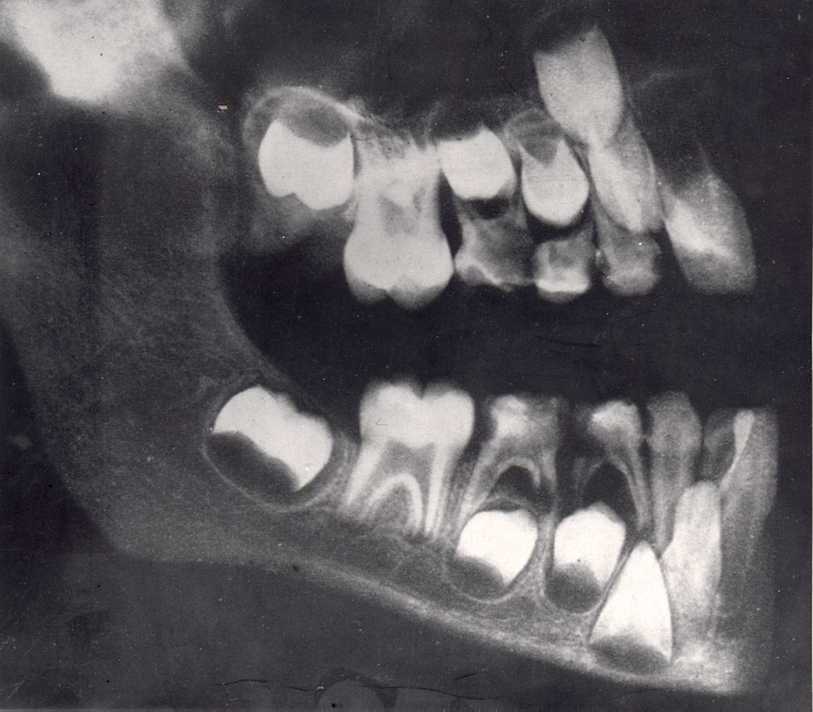

![]() X quang xương và răng hàm trên và dưới trẻ trai 9 tuổi. Theo thứ tự từ Trái sang Phải là mầm răng vĩnh viễn số 7, số 6 đã mọc và bị hỏng do sâu răng. Răng vĩnh viễn số 5, số 4, răng sữa số 3, răng cửa vĩnh viễn số 2, 1 đã mọc. Dưới chân răng sữa số 3 là mầm răng vĩnh viễn số 3 Hiện tượng tiêu chân răng sữa do thân răng vĩnh viễn tì vào ở chân răng số 4 sữa còn lại |